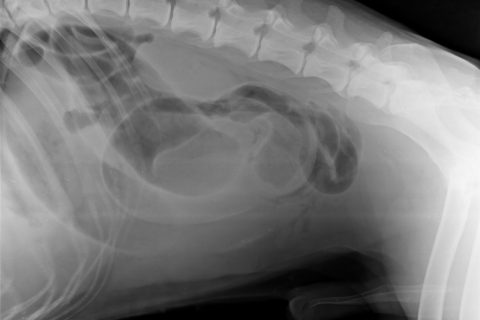

Lažan i fasificiran nalaz mišljenje veterinarske ambulante Lonjica koji dokazuje moje tvrdnje o prikrivanju istine što je detaljno pojašnjeno u video zapisu.

Niti 13.4. niti 14.4. nije rađena ultrazvučna pretraga koja je ovdje napisana za 13. travanj 2021. Nije uočena nikakva tvorba u području mezogastrija. Rtg koji je rađen dva dana, nije ovdje niti spomenut. Nisam odbio patohistološku pretragu i razudbu jer mi ista nije niti ponuđena. To su trebali sami napraviti, ali nisu jer bi se otkrila istina.